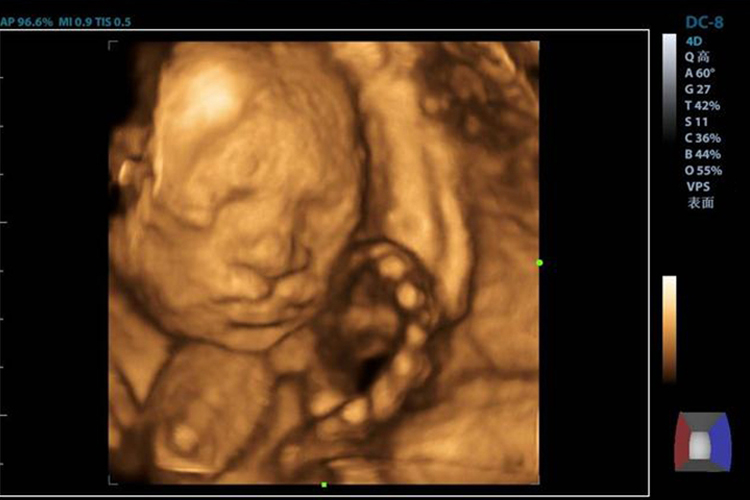

四维彩超是胎儿系统超声筛查的一种方式,一般在孕20-24周进行,可观察到胎儿有无明显的结构畸形,胎儿口唇轮廓在四维彩超图像中可较完整显示。兔唇即唇裂,从四维彩超中可发现胎儿冠状面上唇出现连续中断,横断面则能够观察到胎儿牙槽突回声逐渐中断,正常弧形开始消失,唇裂裂口距离多在2-11.5mm。

临床可根据裂隙大小将唇裂分为三度,其中一度仅表现为唇红裂,上唇皮肤正常;二度唇裂裂隙可达到胎儿上唇皮肤,但未达到其鼻底;三度唇裂的裂隙从唇红达到胎儿鼻底,并且完全张裂。